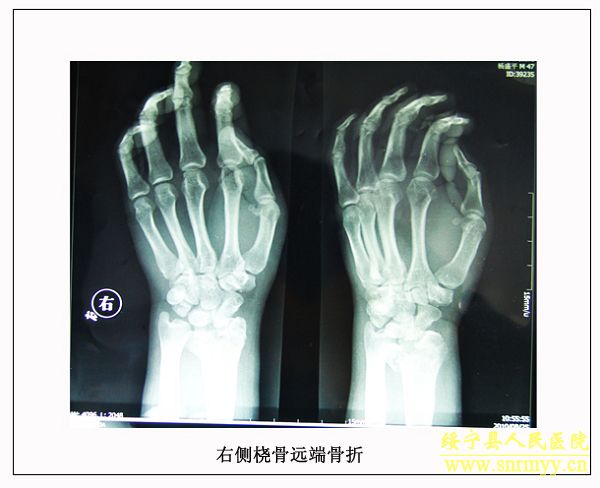

经检查:当时病人体温36.5℃、脉搏105次/分钟、呼吸25次/分钟、血压152/98mmhg,呈昏迷状,头面部、右手、左下肢均不同程度受伤,双侧瞳孔不等大,光反射消失;同时右手臂和左大腿均有骨折。GCS评分:仅4分,根据评分标准(轻度颅脑损伤为12—15分、中度为8—12分、重度为5—8分、极重度为3—5分)该病人属于极重度颅脑损伤。CT检查结果为脑干挫裂伤、双侧额叶、左颞叶、右顶叶脑挫裂伤、左侧颞部硬膜外、下血肿,左顶硬膜下血肿,蛛网膜下腔出血,脑室内积血,左侧额部下积液,左眼框内侧壁,枕骨骨折。X光片显示右桡骨粉碎性骨折,左股骨干骨折。诊断为:1、极重度颅脑损伤:(1)脑干挫裂伤。(2)双侧额叶、左颞叶、右顶叶脑挫裂伤。(3)右颞部硬膜外血肿。(4)外伤性蛛网膜下腔出血。(5)枕骨骨折。(6)头皮多处挫裂伤。2、右桡骨粉碎性骨折。3、左股骨干骨折。临床上如此严重的脑损伤死亡率极高,再加上合并多处骨折创伤,病人危在旦夕。